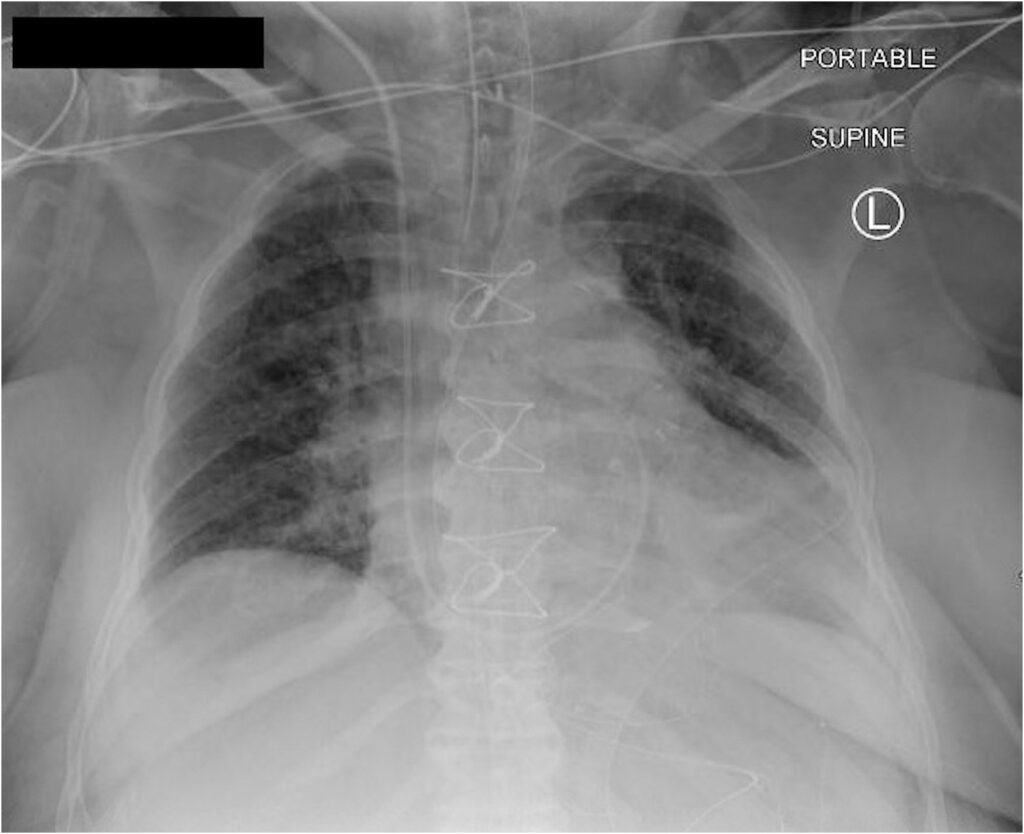

Durante o procedimento, um cateter fino e flexível é inserido, geralmente, através de uma veia no pescoço, virilha ou braço. Com o auxílio de imagens de Raio X, esse cateter é guiado pelo Cardiologista Intervencionista até o lado direito do coração e, em seguida, para a artéria pulmonar.